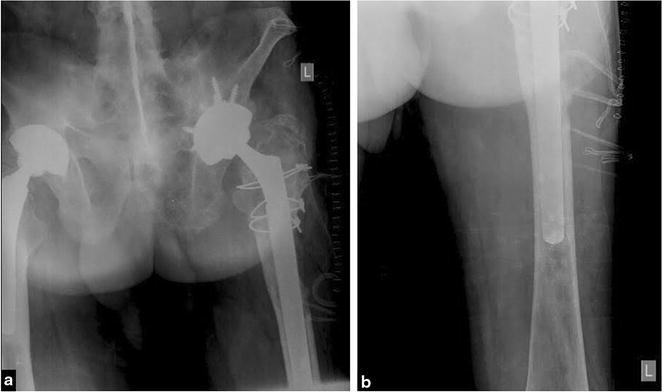

The authors describe clinical and radiologic features, histologic appearance, and treatment of osteogenic osteosarcoma located in the proximal femoral diaphysis associated with an unstable femoral prosthesis following THA in a 65-year-old male patient. The patient with HLA-B27 positive ankylosing spondylitis underwent arthroplasty 15 years ago.

The neoplastic process may be considered as an extraordinary complication of THA and might just be coincidental or the result of some derangement of the healing process in host tissue with no definitely proven hypothesis that the implants or their by-products are carcinogenic. The soluble chemical substances from the implanted prosthetic material are, at least in animals, suspected to play a vital role in the pathogenesis of the neoplastic transformation of the bone tissue. The presented case shall alert orthopedic surgeons to clinical, radiologic, and macroscopic similarities between a malignant tumor and benign lesions caused by wear debris at THA sites. At the examination of plane X-rays of patients with THA loosening, the differential diagnosis should always include osteogenic sarcoma, as well. To our knowledge, there have been only nine cases of THA-related osteogenic osteosarcomas described in the English-language literature.